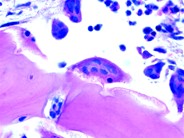

Bone Marrow Aspirate showing osteoblasts (May-Grünwald-Giemsa stain). Osteoblasts are mononucleated cuboidal cells responsible for bone formation. They originate from immature mesenchymal stem cells, which can also differentiate into chondrocytes, muscle, fat, ligaments, and tendon cells. These cells have eccentric nucleus, intensely basophilic cytoplasm and clear region equivalent to the Golgi Complex.